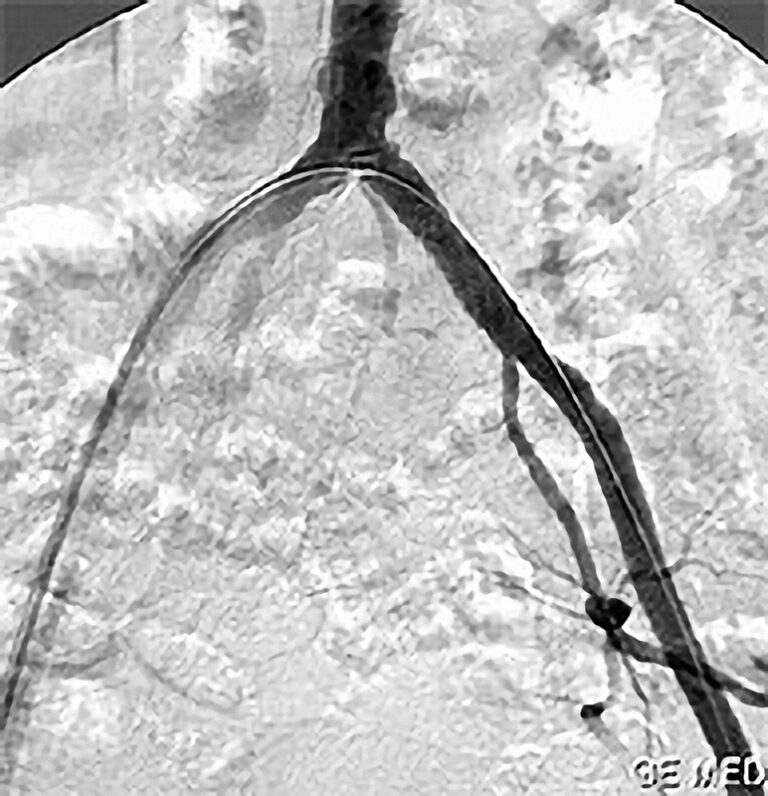

Die PTA (Perkutane Transluminale Angioplastie) im Beckenbereich ist ein minimalinvasives Verfahren zur Behandlung von verengten Beckenarterien. Dabei wird ein dünner Katheter mit einem Ballon über die Leiste in die verengte Arterie eingeführt. Der Ballon wird an der Engstelle entfaltet und dehnt die Arterie auf, um den Blutfluss zu verbessern. Oft wird zusätzlich ein Stent eingesetzt, um die Arterie dauerhaft offen zu halten. Die PTA wird meist in örtlicher Betäubung durchgeführt und ermöglicht eine schnelle Erholung. Sie ist eine bewährte Alternative zur offenen Operation bei Durchblutungsstörungen im Becken- und Beinbereich.